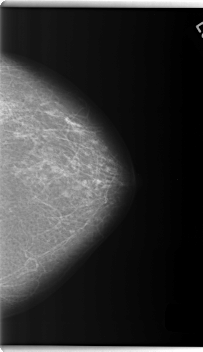

C_0254_1.LEFT_CC

LEFT_CC LINES 5968 PIXELS_PER_LINE 3440 BITS_PER_PIXEL 12 RESOLUTION 50 NON_OVERLAY